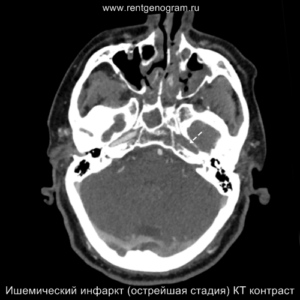

Острая фаза (6 — 24 часа)

В течение острого этапа на МРТ и КТ выявляются все морфологические признаки ишемического инсульта. Область острого ишемического инфаркта визуализируется как зона ↑Т2, ↑Flair, ↑DWI и ↓Т1 ↓ADC. Можно обнаружить тромб в артерии. На КТ в остром этапе также чётко дифференцируется поражённая область, представляющая собой участок с потерей дифференциации мозговых структур и снижением их плотности. Контрастирование в остром периоде не показывает патологических участков с накоплением контраста.